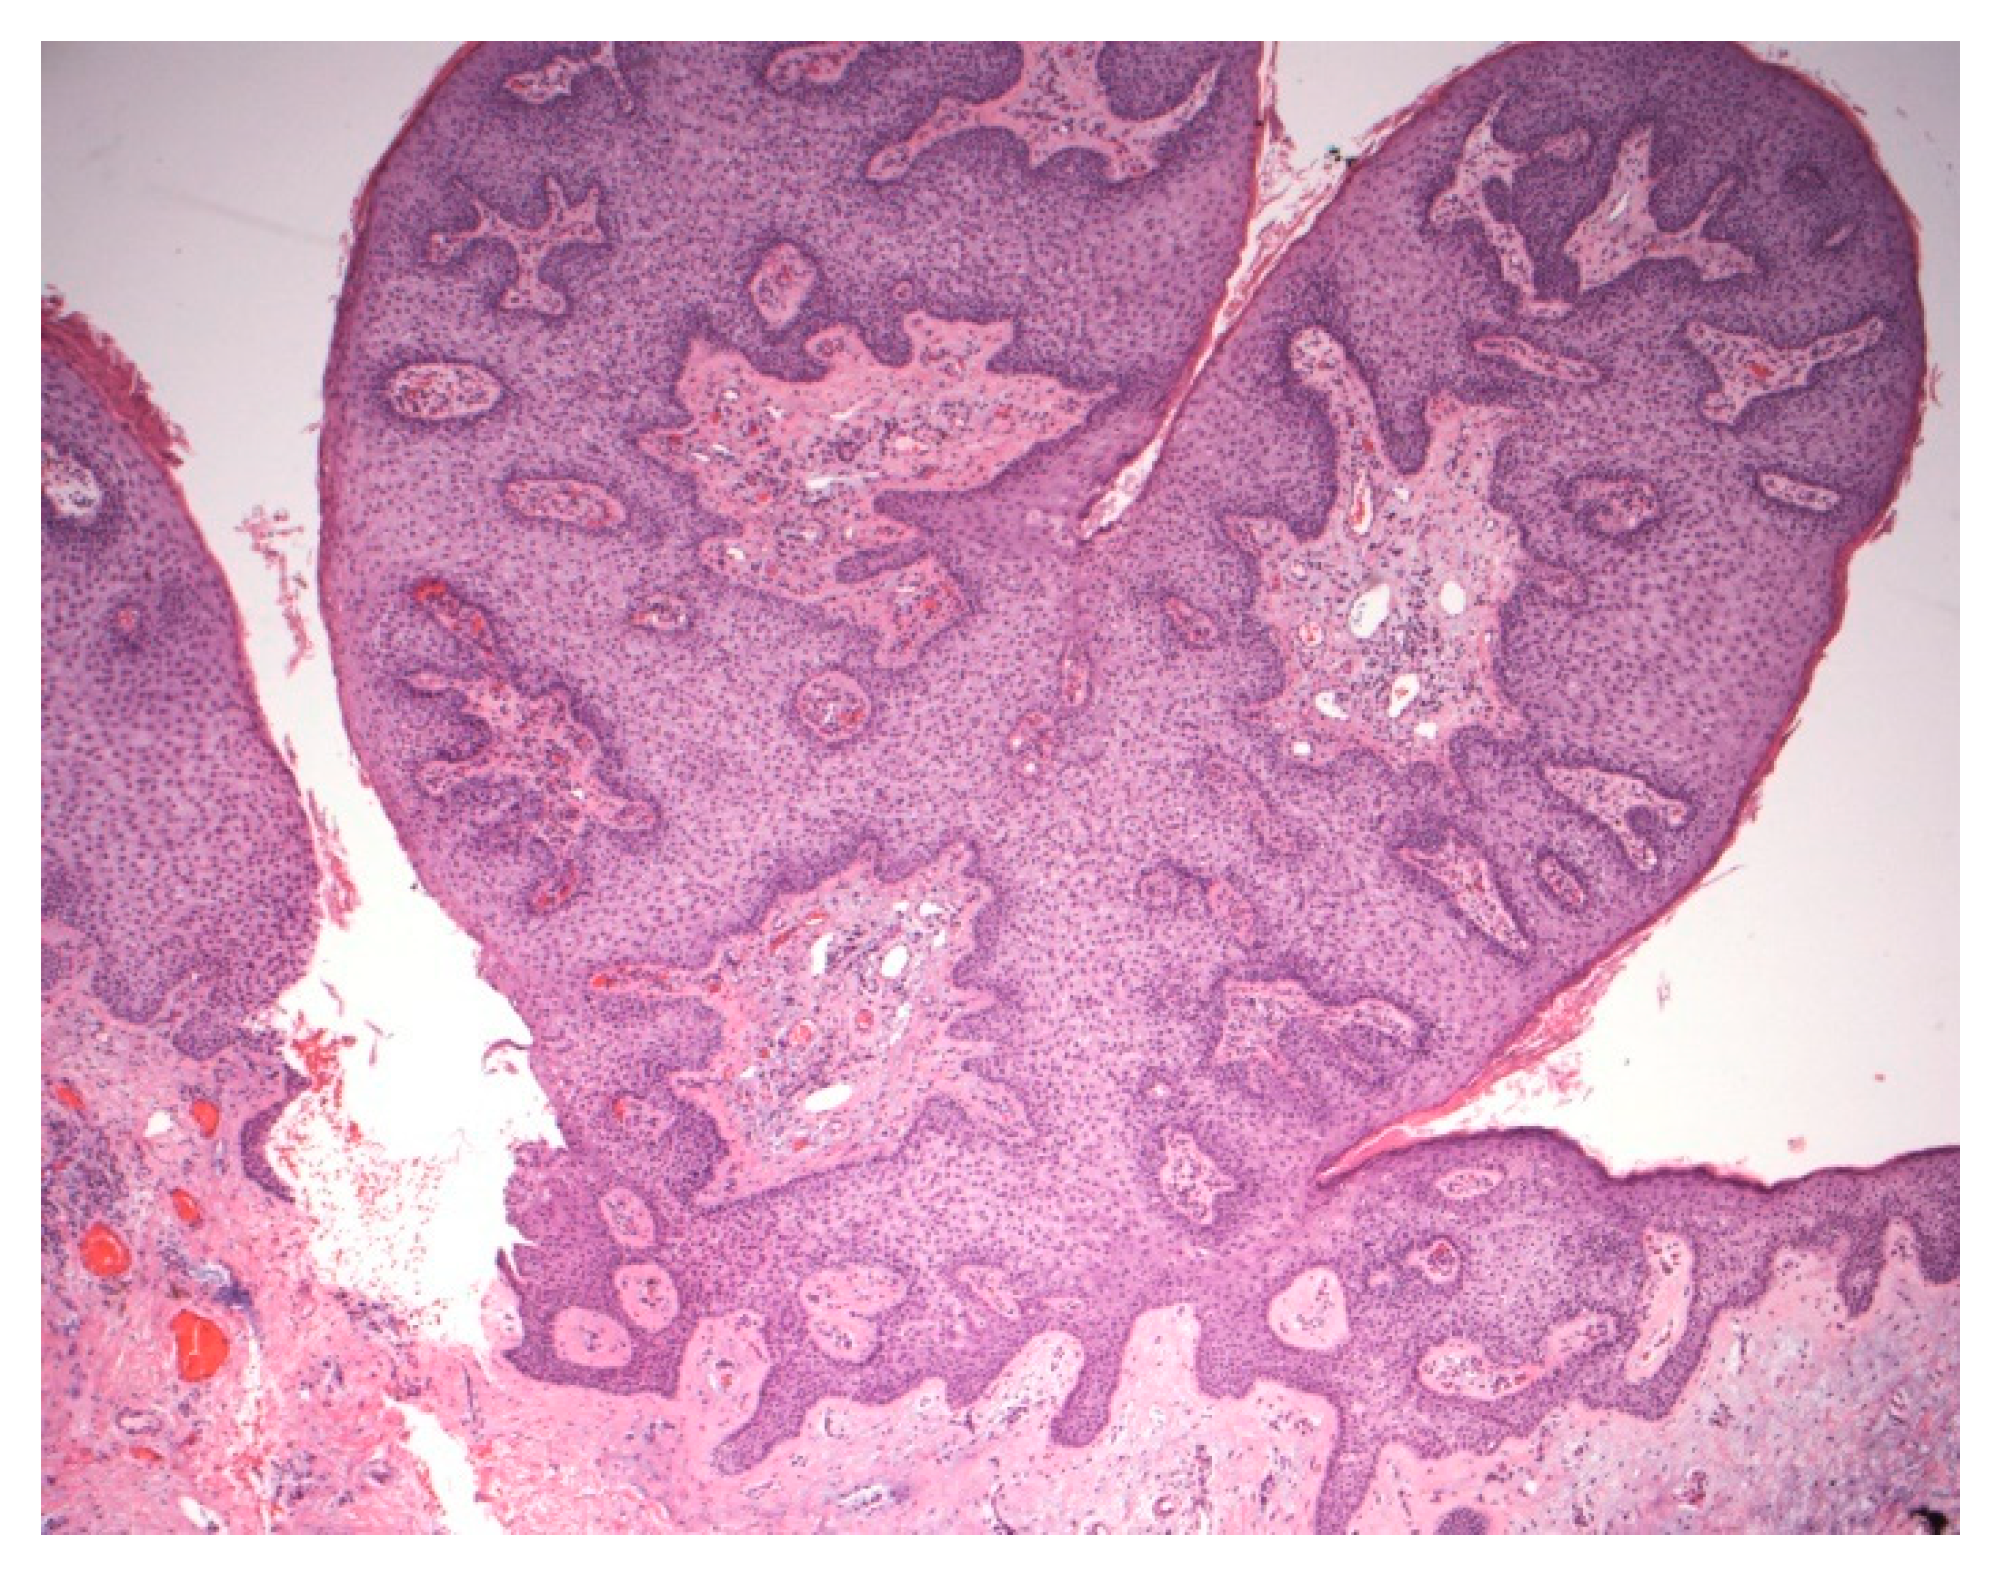

Figure 6.

Polypoid lesion with prominent acanthosis and keratinocytes containing pale cytoplasm. No peripheral palisading or perinuclear vacuoles are noted in this variant.